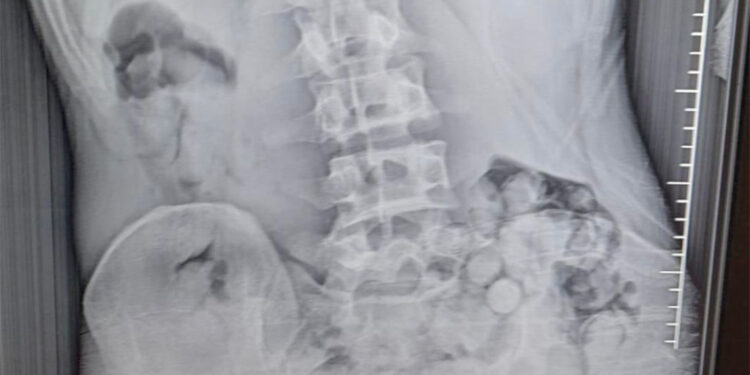

İl Emniyet Müdürlüğü Narkotik Suçlarla Mücadele Şube Müdürlüğü ekipleri, R.B.’nin, Van’dan Samsun’a yolcu otobüsüyle uyuşturucu getireceği bilgisini aldı. Çarşamba ilçesinde durdurulan yolcu otobüsünde arama yapıldı. Aramalarda, herhangi bir uyuşturucu maddeye rastlanmadı. Polis daha sonra şüpheli hareketler sergileyen R.B.’yi gözaltına aldı. Şüphelinin yapılan iç beden muayenesi sonucunda midesinde 51 kapsül halinde toplam 309 gram metamfetamin tespit edildi. Tıbbi müdahalenin ardından taburcu edilen gözaltındaki şüpheliyle ilgili soruşturma sürüyor.